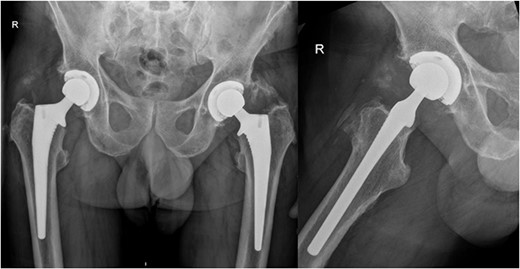

Subsequently, this patient’s case was discussed at our PJI multidisciplinary meeting among the infectious diseases, microbiology, and orthopaedic teams. A consensus decision was made to treat the patient with a 12-week course of IV Vancomycin given the clinical presentation, radiological, and intraoperative findings. After completing his 12 weeks of IV antibiotics, his inflammatory markers returned to normal limits (Fig. 5). At 6-month follow-up, our patient was mobilizing independently without any signs of infection recurrence. His radiographs showed the implant was in a satisfactory position with no evidence of loosening (Fig. 6).

AP pelvis and lateral right hip radiographs at 6 months post debridement, antibiotics, implant retention (DAIR) procedure.